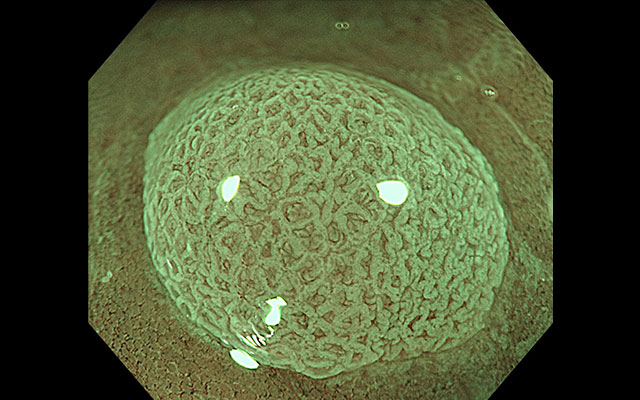

内視鏡診断と腸内細菌の研究です。将来がんは治る病気になるとしても、今この時代にできることは何かを考えると、結論は「内視鏡一択」。大腸がんは良性ポリープ→がん化が基本なので、良性のうちにポリープを取る、早期がんを内視鏡で取ることが重要です。今、健康診断で主流は検便検査ですが、良性ポリープや早期がんは血が出ないことも多く、便潜血が発見される頃には既に進行がんになっている可能性が高いのです。私は学位取得後、佐野病院において、内視鏡分野で世界レベルの佐野先生から最先端の技術を学びました。最初は技術不足で怒られることもありましたが、そこから写真・診断の精度に徹底的にこだわるようになりました。開院した後も、「美しい写真に正しい診断が宿る」という哲学のもと、関西のクリニックでは当院が最初に導入した最新の内視鏡機器(NBI+TXI™モード)を駆使し、微細な病変も見逃しません。高性能機材を入れても、誰でも同じ写真が撮れるわけではありません。0.1mm単位で合わせる技術では誰にも負けない自信があります。一般的な指標(ADR)ではなく、将来的ながんリスクに直結する「腺腫の個数(APC)」にこだわり、徹底的なリスク管理を行います。研究者としての科学的視点と、臨床医としての技術を融合させ、お一人おひとりに最適な医療と腸活を提案します。